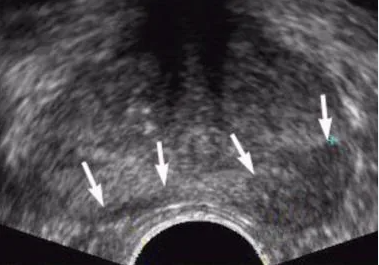

경직장 전립선초음파, 전립선암 특이항원(PSA)검사